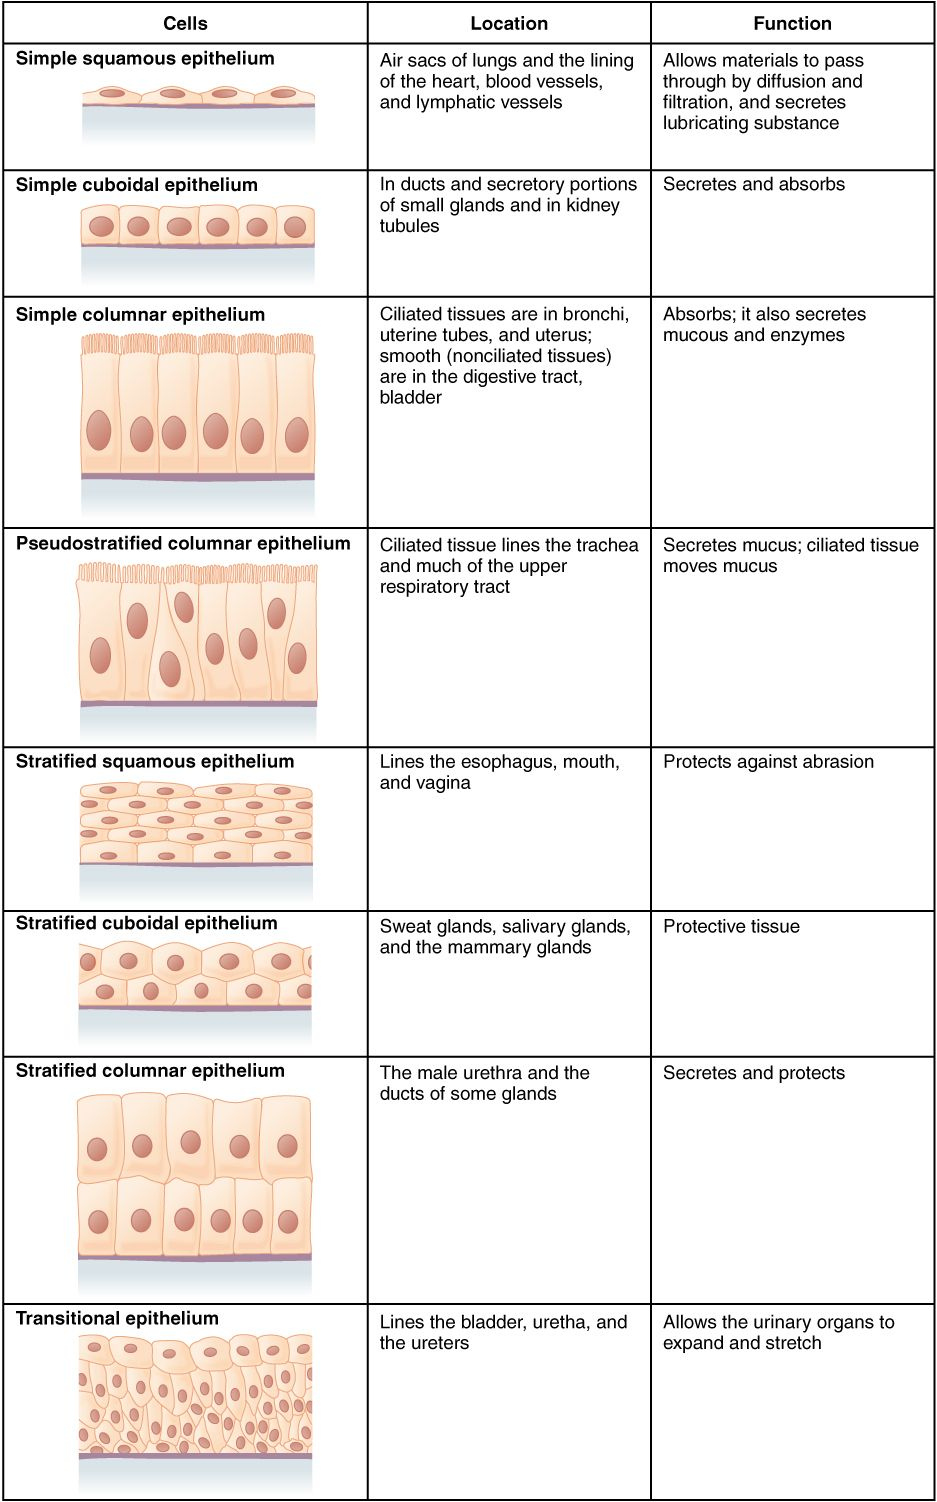

Anatomy worksheets aid you discover the anatomy of numerous organs. You can also learn concerning the mitral valve, which shields the opening between the left atrium and also the ventricle.

Anatomy worksheets are likewise beneficial for students to learn about the heart. They can find out the features of heart muscular tissues and just how they influence the heart’s outcome. For instance, the heart has two valves, the left mitral shutoff as well as the right tricuspid valve. Besides, they can learn more about the blood circulation and also its parts.

Anatomy worksheets are available in a range of styles, consisting of color and labeled versions. They are designed for grade school pupils. These printable worksheets are great for students, instructors, and those interested in natural wellness, physiotherapy, as well as massage therapy.